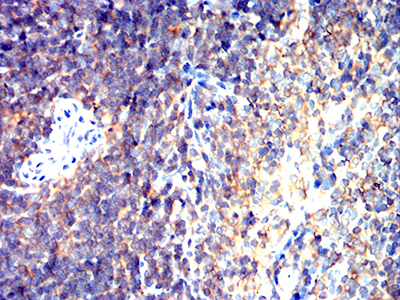

Immunohistochemical analysis of paraffin-embedded human rectum cancer tissues using CD163 mouse mAb with DAB staining.

-

Immunohistochemical analysis of paraffin-embedded Mouse spleen using CD163 mouse mAb with DAB staining.